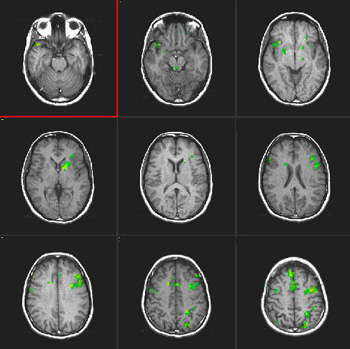

| Images |

| Activation |

The left hemisphere shows predominant activation. The following areas were activated: Broca's, left posterior portion of middle and inferior temporal gyri (Brodman's 37), left parietal and left premotor strip. Wide activation is seen in the inferior aspect of the occipital lobes. The main activation on the right is located in the inferior aspect of the frontal lobe (Brodman's 11), a finding consistently seen in this paradigm. |